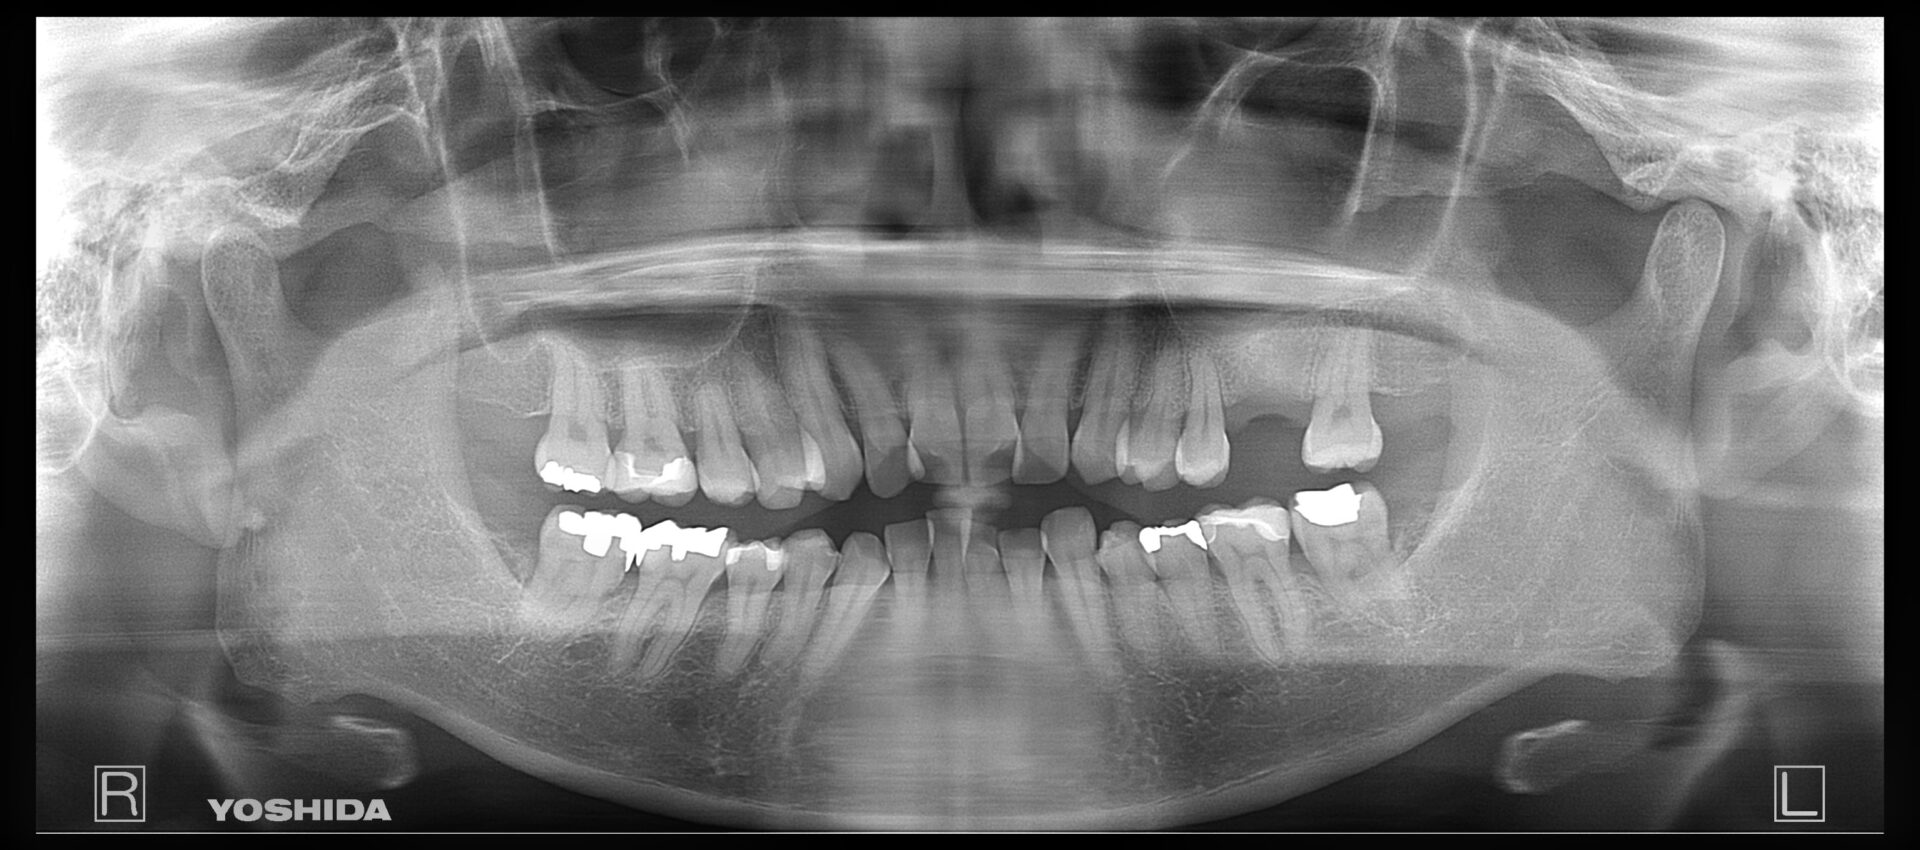

左下7番部にエナメル上皮腫(良性腫瘍)が認められた患者様が、将来的にインプラント治療をご希望されました。

まずは安全を最優先に、口腔外科にて腫瘍の摘出手術を行っていただきました。

手術後は、インプラントを支えるための骨がどの程度回復するか慎重に経過を観察し、約2年間、骨の再生を待ちながらフォローアップを続けました。しかし、残念ながら想定したほど骨量が回復せず、理想的な位置(もう少し奥の部位)にインプラントを埋入することが難しい状態でした。

そこで、工学的・解剖学的条件を総合的に検討し、歯科技工士とも綿密に相談した上で、安全性と長期安定性を優先し、手前側の位置にインプラントを埋入するという治療計画に変更しました。

結果としてインプラントは良好に骨と結合し、現在は問題なくお食事もできており、とても満足して生活されているとのことです。

難症例ではありましたが、口腔外科との連携、慎重な経過観察、そして適切な位置へのインプラント埋入により、安全かつ確実な治療結果を得ることができました。

R5.4

左下7のインプラント埋入を検討

R7.5

4ヶ月前に埋入したインプラントの経過観察

R7.12

11ヶ月慎重に様子を見て上部の被せ物を被せることができました

費用 約47万円

治療期間 12ヶ月